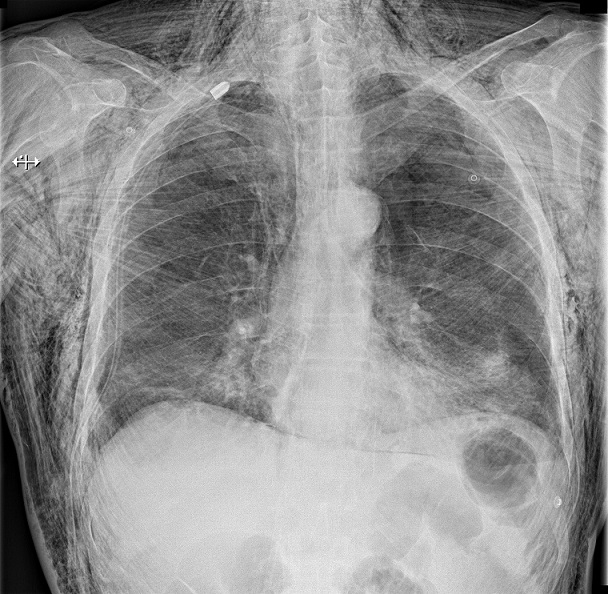

Massive subcutaneous emphysema after traumatic pneumothorax

A 52-year-old man was admitted to our hospital emergency room for dyspnea and extensive chest swelling. He had a right chest trauma after falling over the bathtub. He was hemodynamically stable and on physical examination he had right chest hypoventilation with hypoxemia. The swelling quickly progressed to the cervical region and the skin crackled. Chest X-ray revealed a right pneumothorax with massive subcutaneous emphysema. He was treated by chest drainage and both the emphysema and the pneumothorax completely resolved several days later. Subcutaneous emphysema is usually a benign, self-limiting condition requiring only conservative management. The main risk of subcutaneous emphysema is the massive accumulation of air in the deeper tissue planes that can compromise the life of the patient. This accumulation can substantially compress the trachea and the great vessels, which can severely compromise the airway, venous return, and blood flow to the head and neck. Many techniques have been shown to provide effective treatment. Placing a chest tube and increasing the suction is the most effective and safe option in patients developing subcutaneous emphysema following pneumothorax. Insertion of a drain into the subcutaneous tissue provides rapid relief, aided or not by regular compressive massage. Infraclavicular incisions are also effective, but are noted to be more invasive and carry the potential for cosmetic defect. The optimal approach to patients who present with subcutaneous emphysema is not always apparent. A watchful-waiting attitude is recommended in limited subcutaneous emphysema. Indications must be carefully considered on an individual patient basis.